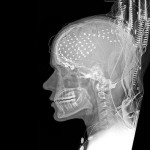

Si usted empezo a leer este articulo lo más probable es que este oyendo hablar a si mismo, incluso si usted no dice estas palabras en voz alta. Este discurso llamado como «monólogo interior» que se escucha dentro de nuestras cabezas es un fenómeno sin examinar pero importante. Un nuevo estudio analiza un posible mecanismo cerebral que podría explicar cómo oímos esta voz interior en ausencia de sonido real.

En dos experimentos, el investigador Mark Scott de la Universidad de Columbia Británica encontró evidencia de que una señal del cerebro llamada señal de descarga corolario nos ayuda a distinguir las experiencias sensoriales que producimos nosotros mismos de las producidas por estímulos externos y esta juega un papel importante en nuestras experiencias de discurso interno.

La descarga corolario es un tipo de señal predictivo generado por el cerebro que ayuda a explicar, por ejemplo, por qué las personas pueden hacernos cosquillas, pero nosotros no podemos hacernos cosquillas a nosotros mismos. La señal predice nuestros propios movimientos y cancela efectivamente la sensación de cosquillas. Y el mismo mecanismo desempeña un papel en la forma en nuestro sistema auditivo procesa el habla. Cuando hablamos, se genera una copia interna del sonido de nuestra voz en paralelo con el sonido externo que oímos.

Scott, especuló que la copia interna de nuestra voz producida por la descarga corolario se puede generar incluso cuando no hay ningún sonido externo, lo que significa que el sonido que oímos cuando hablamos dentro de nuestras cabezas es en realidad la predicción interna del sonido de nuestra propia voz.